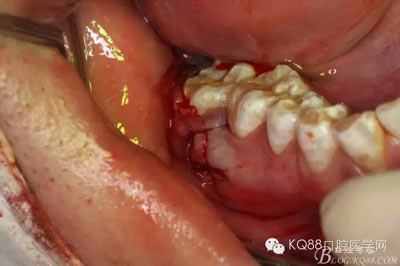

圖7.粘膜瓣似乎粘連,非常難翻,結(jié)果48還在骨頭里,頰側(cè)骨壁沒缺失呀,CBCT有問題?

圖8.不管它,眼見為實(shí),去骨,發(fā)現(xiàn)48與周圍骨質(zhì)沒有界限,幾乎完全粘連

圖9.不斷的耐心去骨,發(fā)現(xiàn)48被下方的囊性改變趕到舌側(cè)。

圖10 開始分牙,術(shù)中分牙經(jīng)歷非??部?,鉆頭操作異常困難,因?yàn)?8倍囊性改變推至舌側(cè)。

圖13.把48干掉,繼續(xù)戰(zhàn)斗,摘除下方囊腫,結(jié)果翻瓣超過前庭溝時,發(fā)現(xiàn)頰側(cè)骨板缺失,與48牙槽窩完全貫通

注意看:骨間隔上方是48牙槽窩,下方是囊腔。有點(diǎn)后悔翻瓣有點(diǎn)過淺了。

圖14.徹底清理囊腔內(nèi)的上皮組織,頰側(cè)骨壁缺失嚴(yán)重。